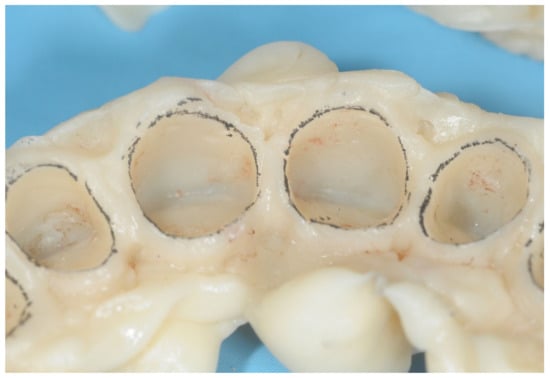

- Primary progressive reduction: This procedure is performed by using the bur with an inclination of 30° so that only the final part of the bur is in contact with the tooth structure. The bur is kept more coronal than the previously measured depth of the gingival sulcus of that site. In this way, the tissue of the root surface and a small component of the internal part of the gingival sulcus is removed. This reduction will result in a small step at the level corresponding to the tip of the bur. At this point, the preparation is “bur-shaped” as with most of the complete crown techniques (Figure 3).

- Secondary progressive reduction: The previously performed reduction of tooth structure and the push of the bur on the gingival margin, together with the unavoidable gingitage, will result in an augmented space between the tooth structures and the gingival margin. This allows the clinician to obtain better vision and access to the deepest parts of the sulcus and, therefore, to see and remove any calculus, steps, grooves, or undercuts from the root surfaces. Using a “toe-heel” technique, the apical part of the root surface is structured, creating the edgeless profile of this preparation. Then, the coronal portion of the abutment is reduced by using a bur with reverse angulation. In this phase, it is also necessary to connect the different reduction planes created during the various stages (Figure 4).